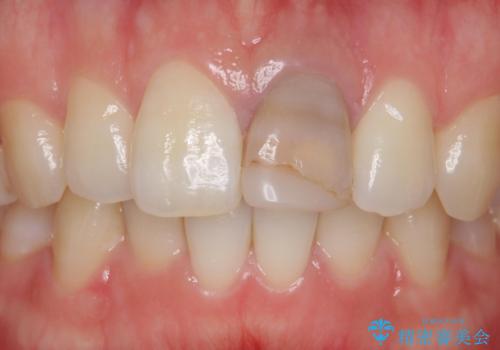

前歯を綺麗にしたい e-maxクラウンでの修復

- 前歯のかぶせ物の変色を主訴に来院された患者様です。

根管治療からのやり直しはご希望されませんでした。

今回はe-maxクラウンで修復していきます。

歯のガタつきも解消することができました。

e-maxクラウンでは仮着ができませんが、今回は一回でご満足いただける修復ができました。